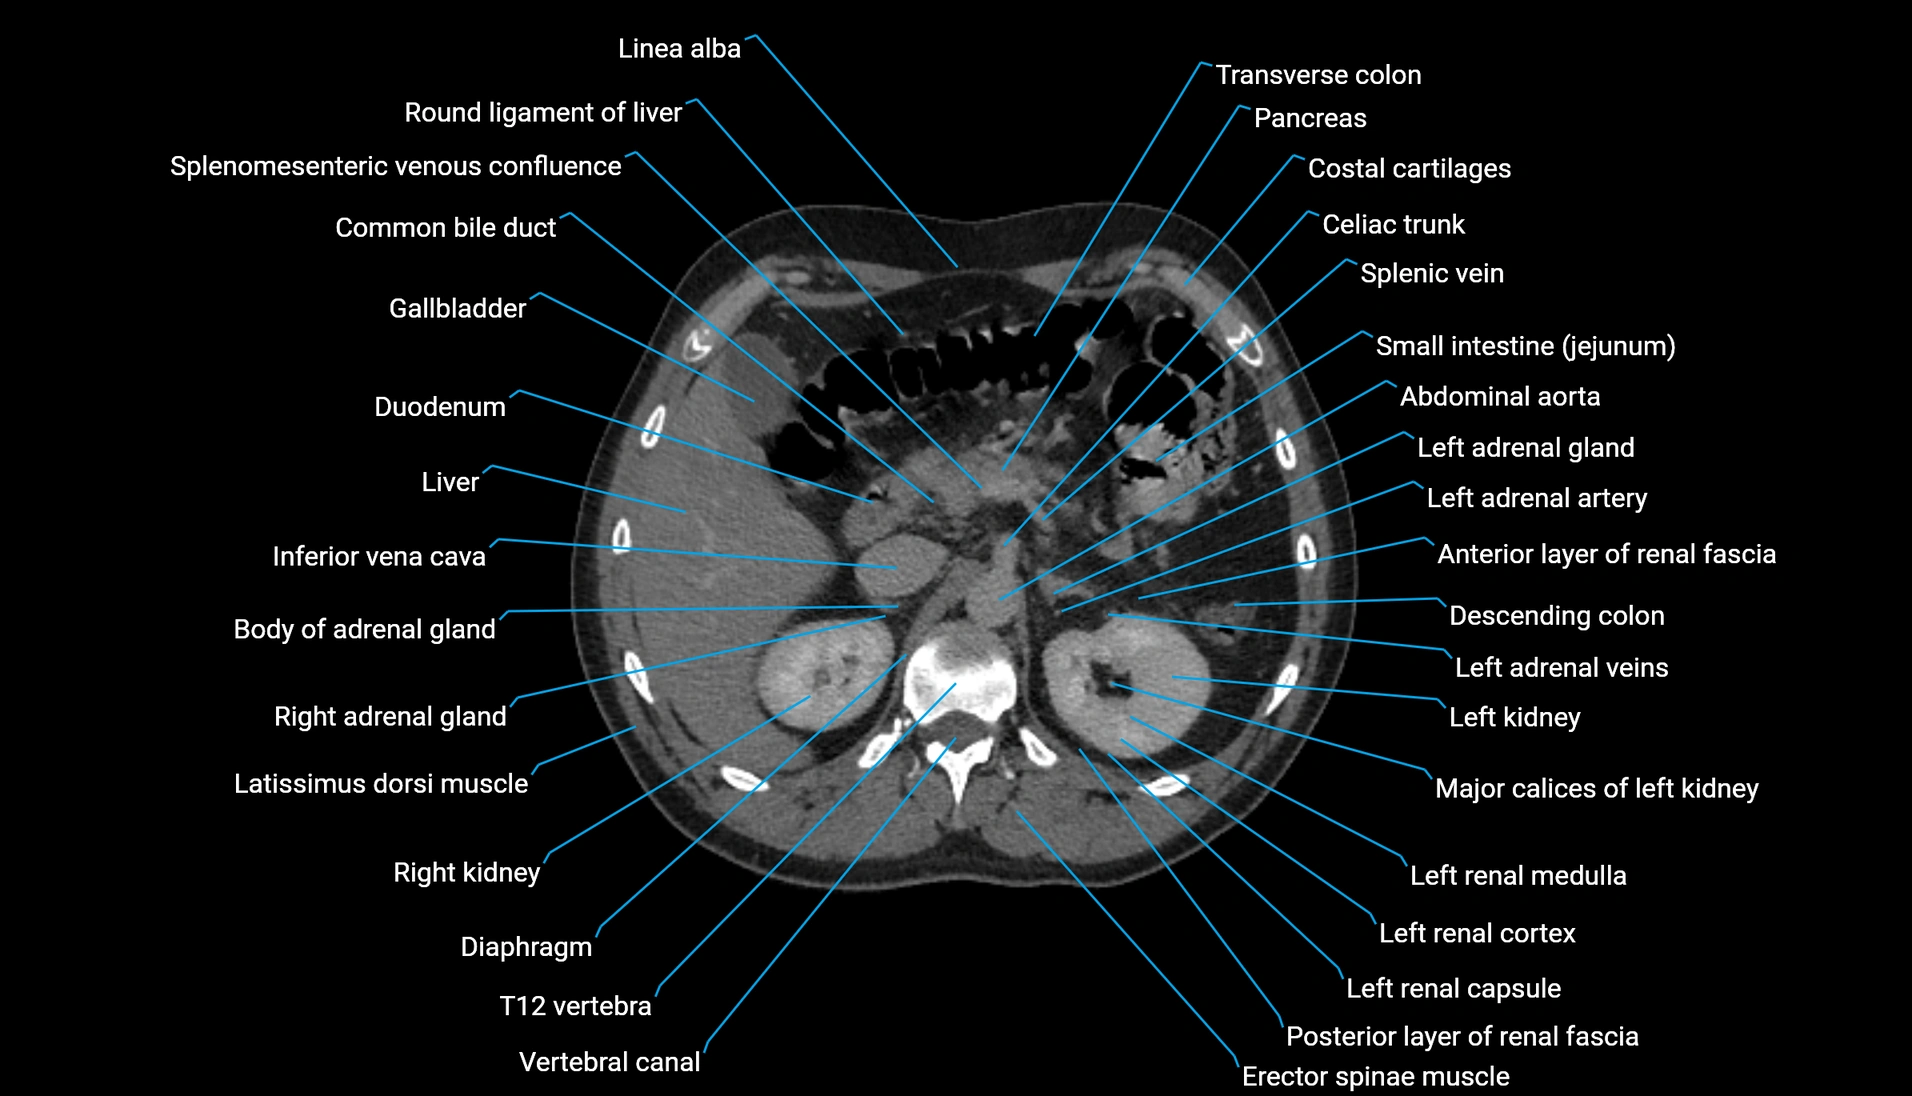

CT Appearance

Non-contrast CT:

-

Demonstrates cortical bone of acetabular rim in excellent detail

Detects fractures, dysplasia, retroversion, or bony overcoverage (pincer impingement)

3D reconstructions used in preoperative hip surgery planning

CT VRT 3D image

CT image